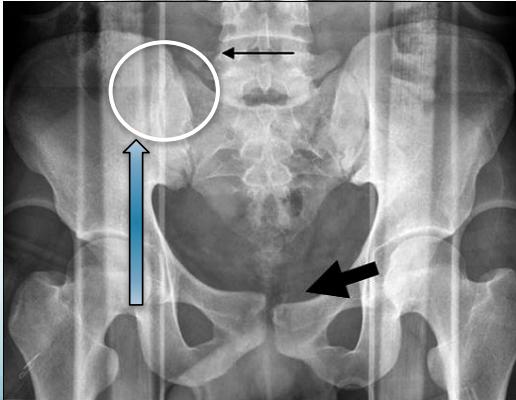

Transverse Processes Fracture

- Avulsion fracture of Transverse Processes

- Isolated, stable

- Supportive treatment

- Fracture of L5 transverse process (Red flag)

- Might indicate a shear injury of pelvis